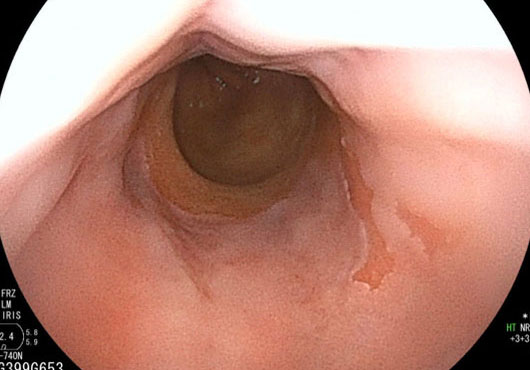

逆流性食道炎

強い酸性の胃液(胃酸)が胃の内容物とともに食道に逆流し、食道の粘膜に炎症が生じる病気です。胃酸が増えすぎてしまったり、胃酸の逆流を防ぐ機能がうまく働かなかったりすることで起こります。胃酸がのどまで上がってきて酸っぱいと感じるようになったり、胸やけやのどがヒリヒリしたりして不快感が続きます。喫煙、飲酒などの生活習慣や加齢、肥満、姿勢、食道裂孔ヘルニアなどが原因となります。